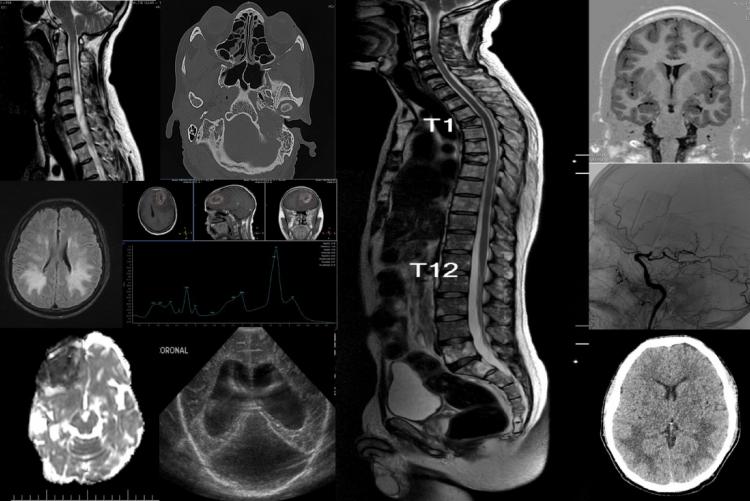

Les neuroradiologues ont une formation en radiologie diagnostique pour étudier diverses maladies telles que les accidents vasculaires cérébraux, les maladies démyélinisantes, les maladies neurodégénératives, les tumeurs cérébrales, les cancers de la tête et du cou, les maladies neurovasculaires, les traumatismes, les douleurs dorsales et d'autres maladies neurologiques.

Les principales modalités d'imagerie sont la tomodensitométrie (Scanner) et l'imagerie par résonance magnétique (IRM).